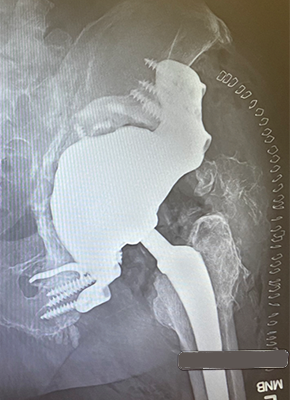

Case Studies

With more than 40,000 individual solutions during the last 50 years, we have been able to gain a lot of experience in this field. We already provided successful solutions for nearly every anatomical region of the human body. See some of our case studies below…